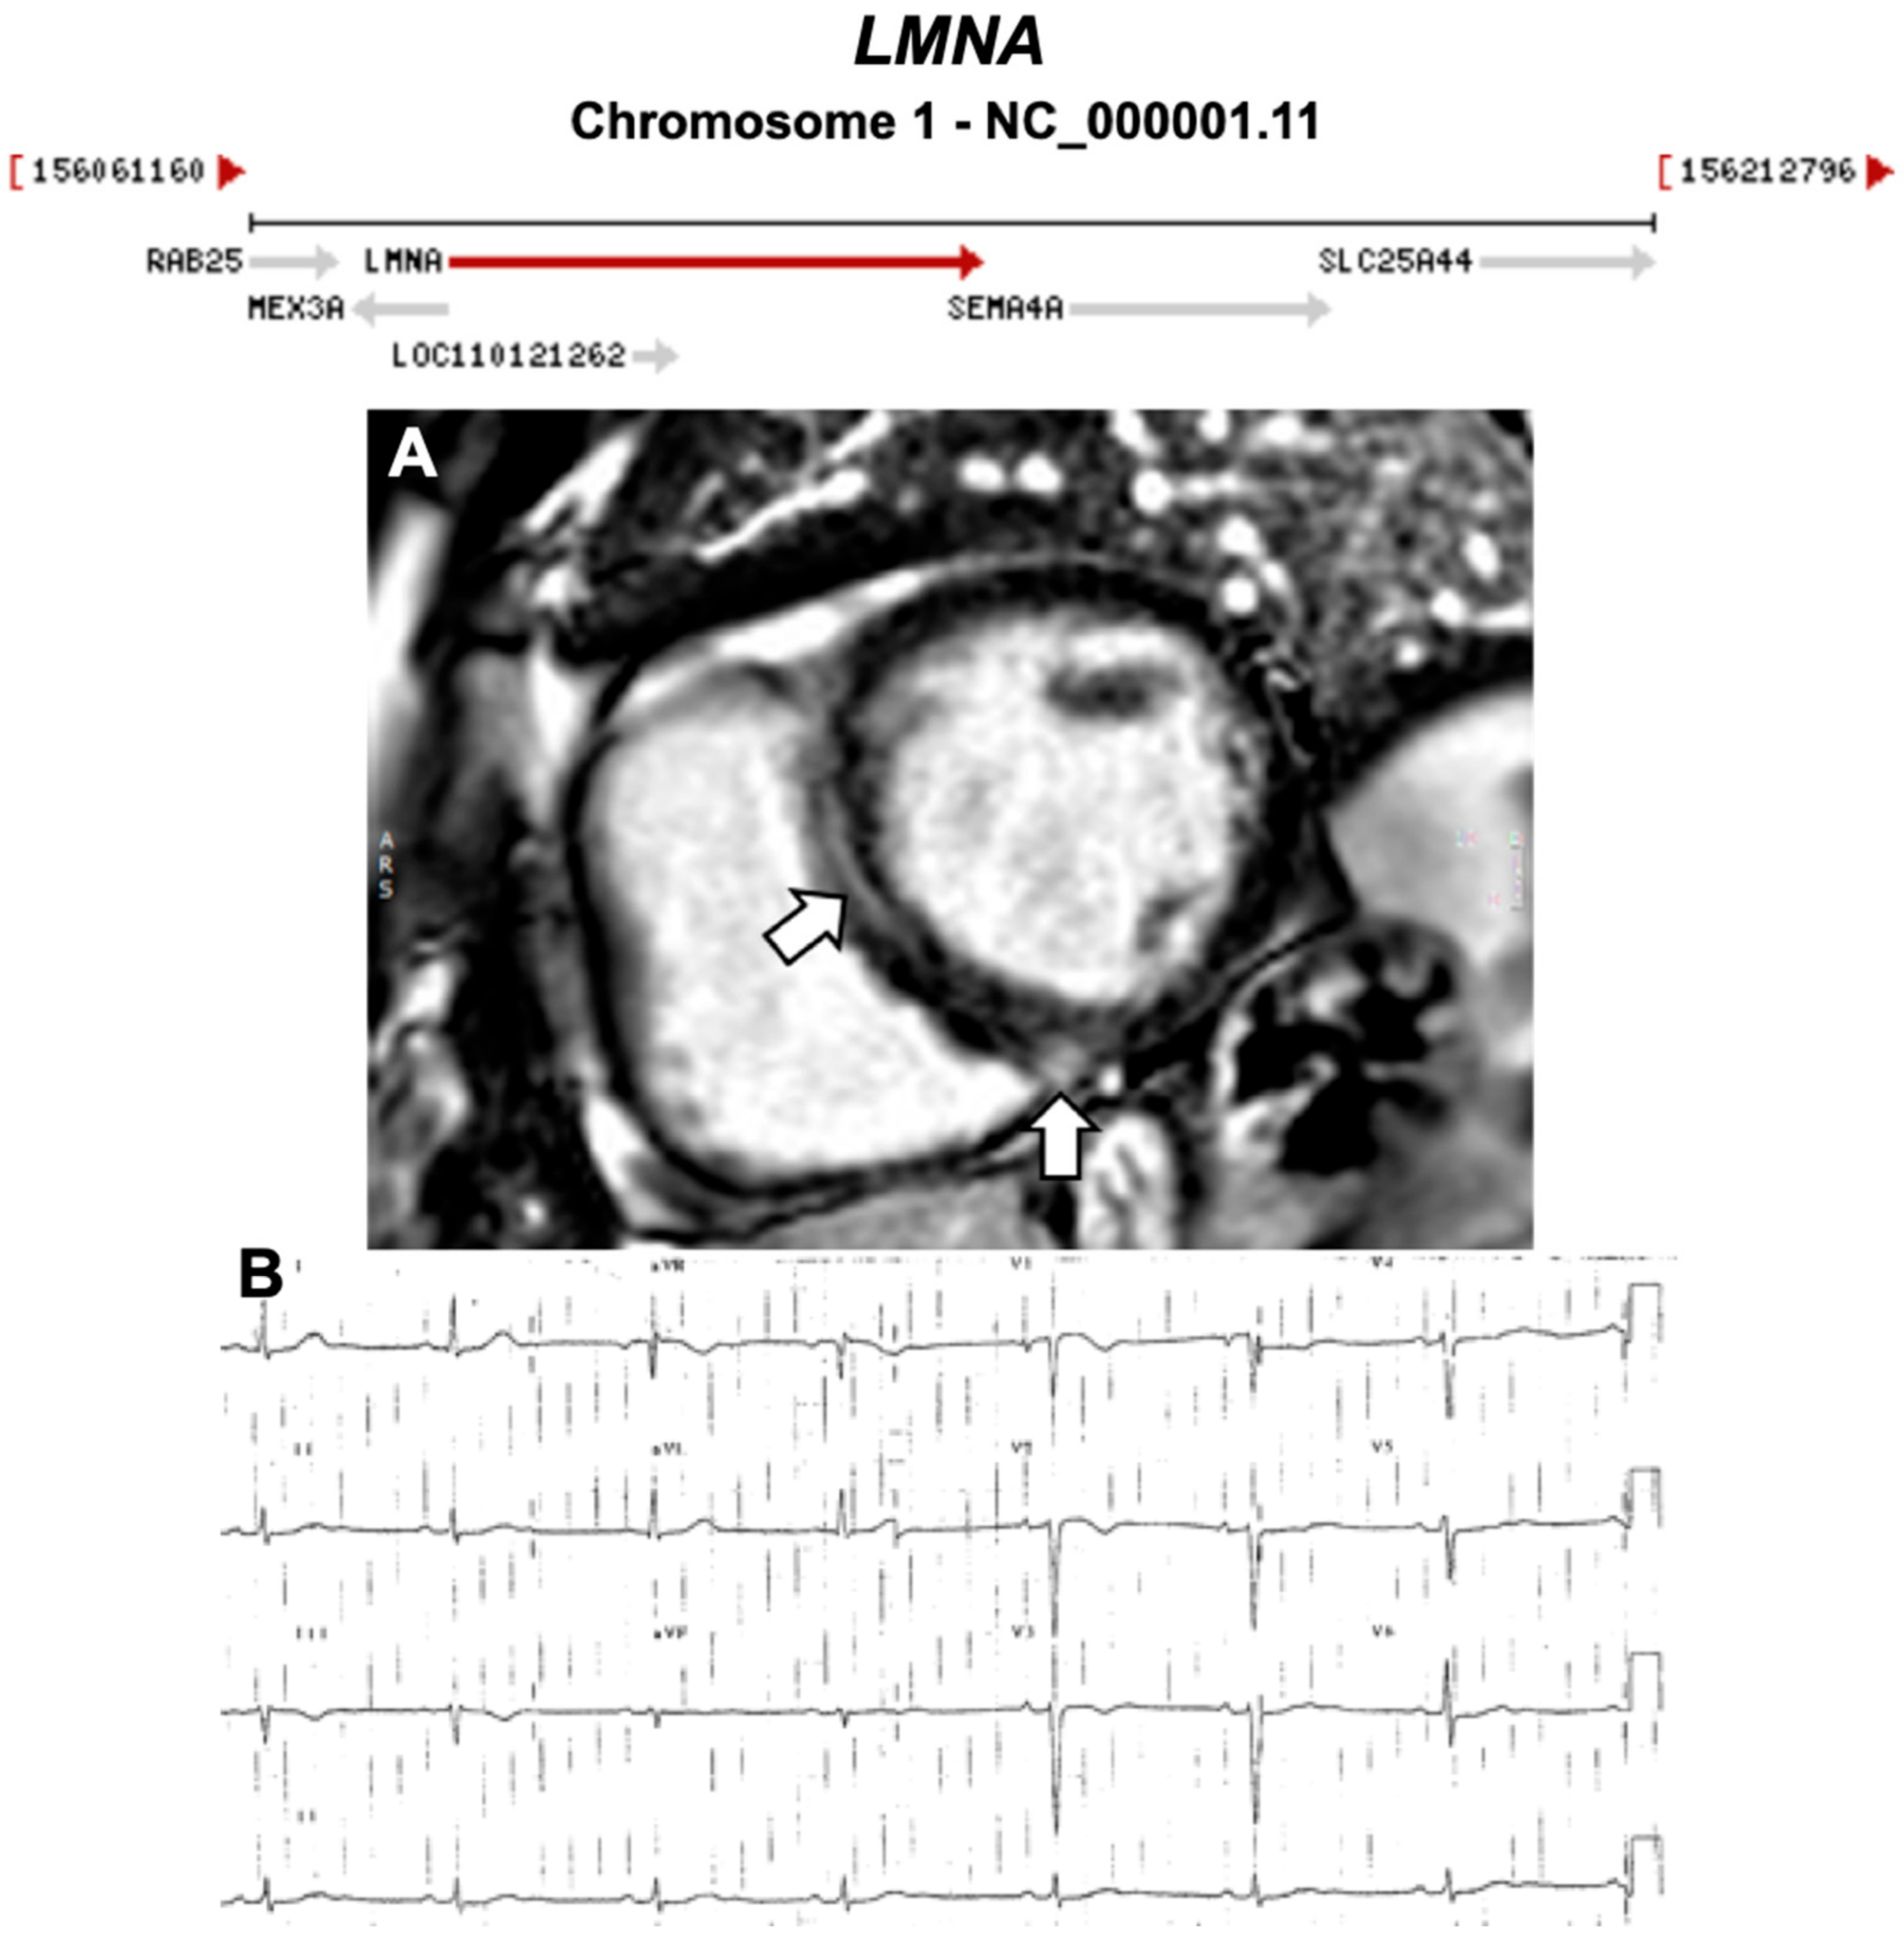

| LMNA | Nuclear Intermediate Filament | 3–4% | AD | LV, BiV | - | 1q22; 17 | DCM, Lipodystrophies, Myopathies | Limited for ARVC |